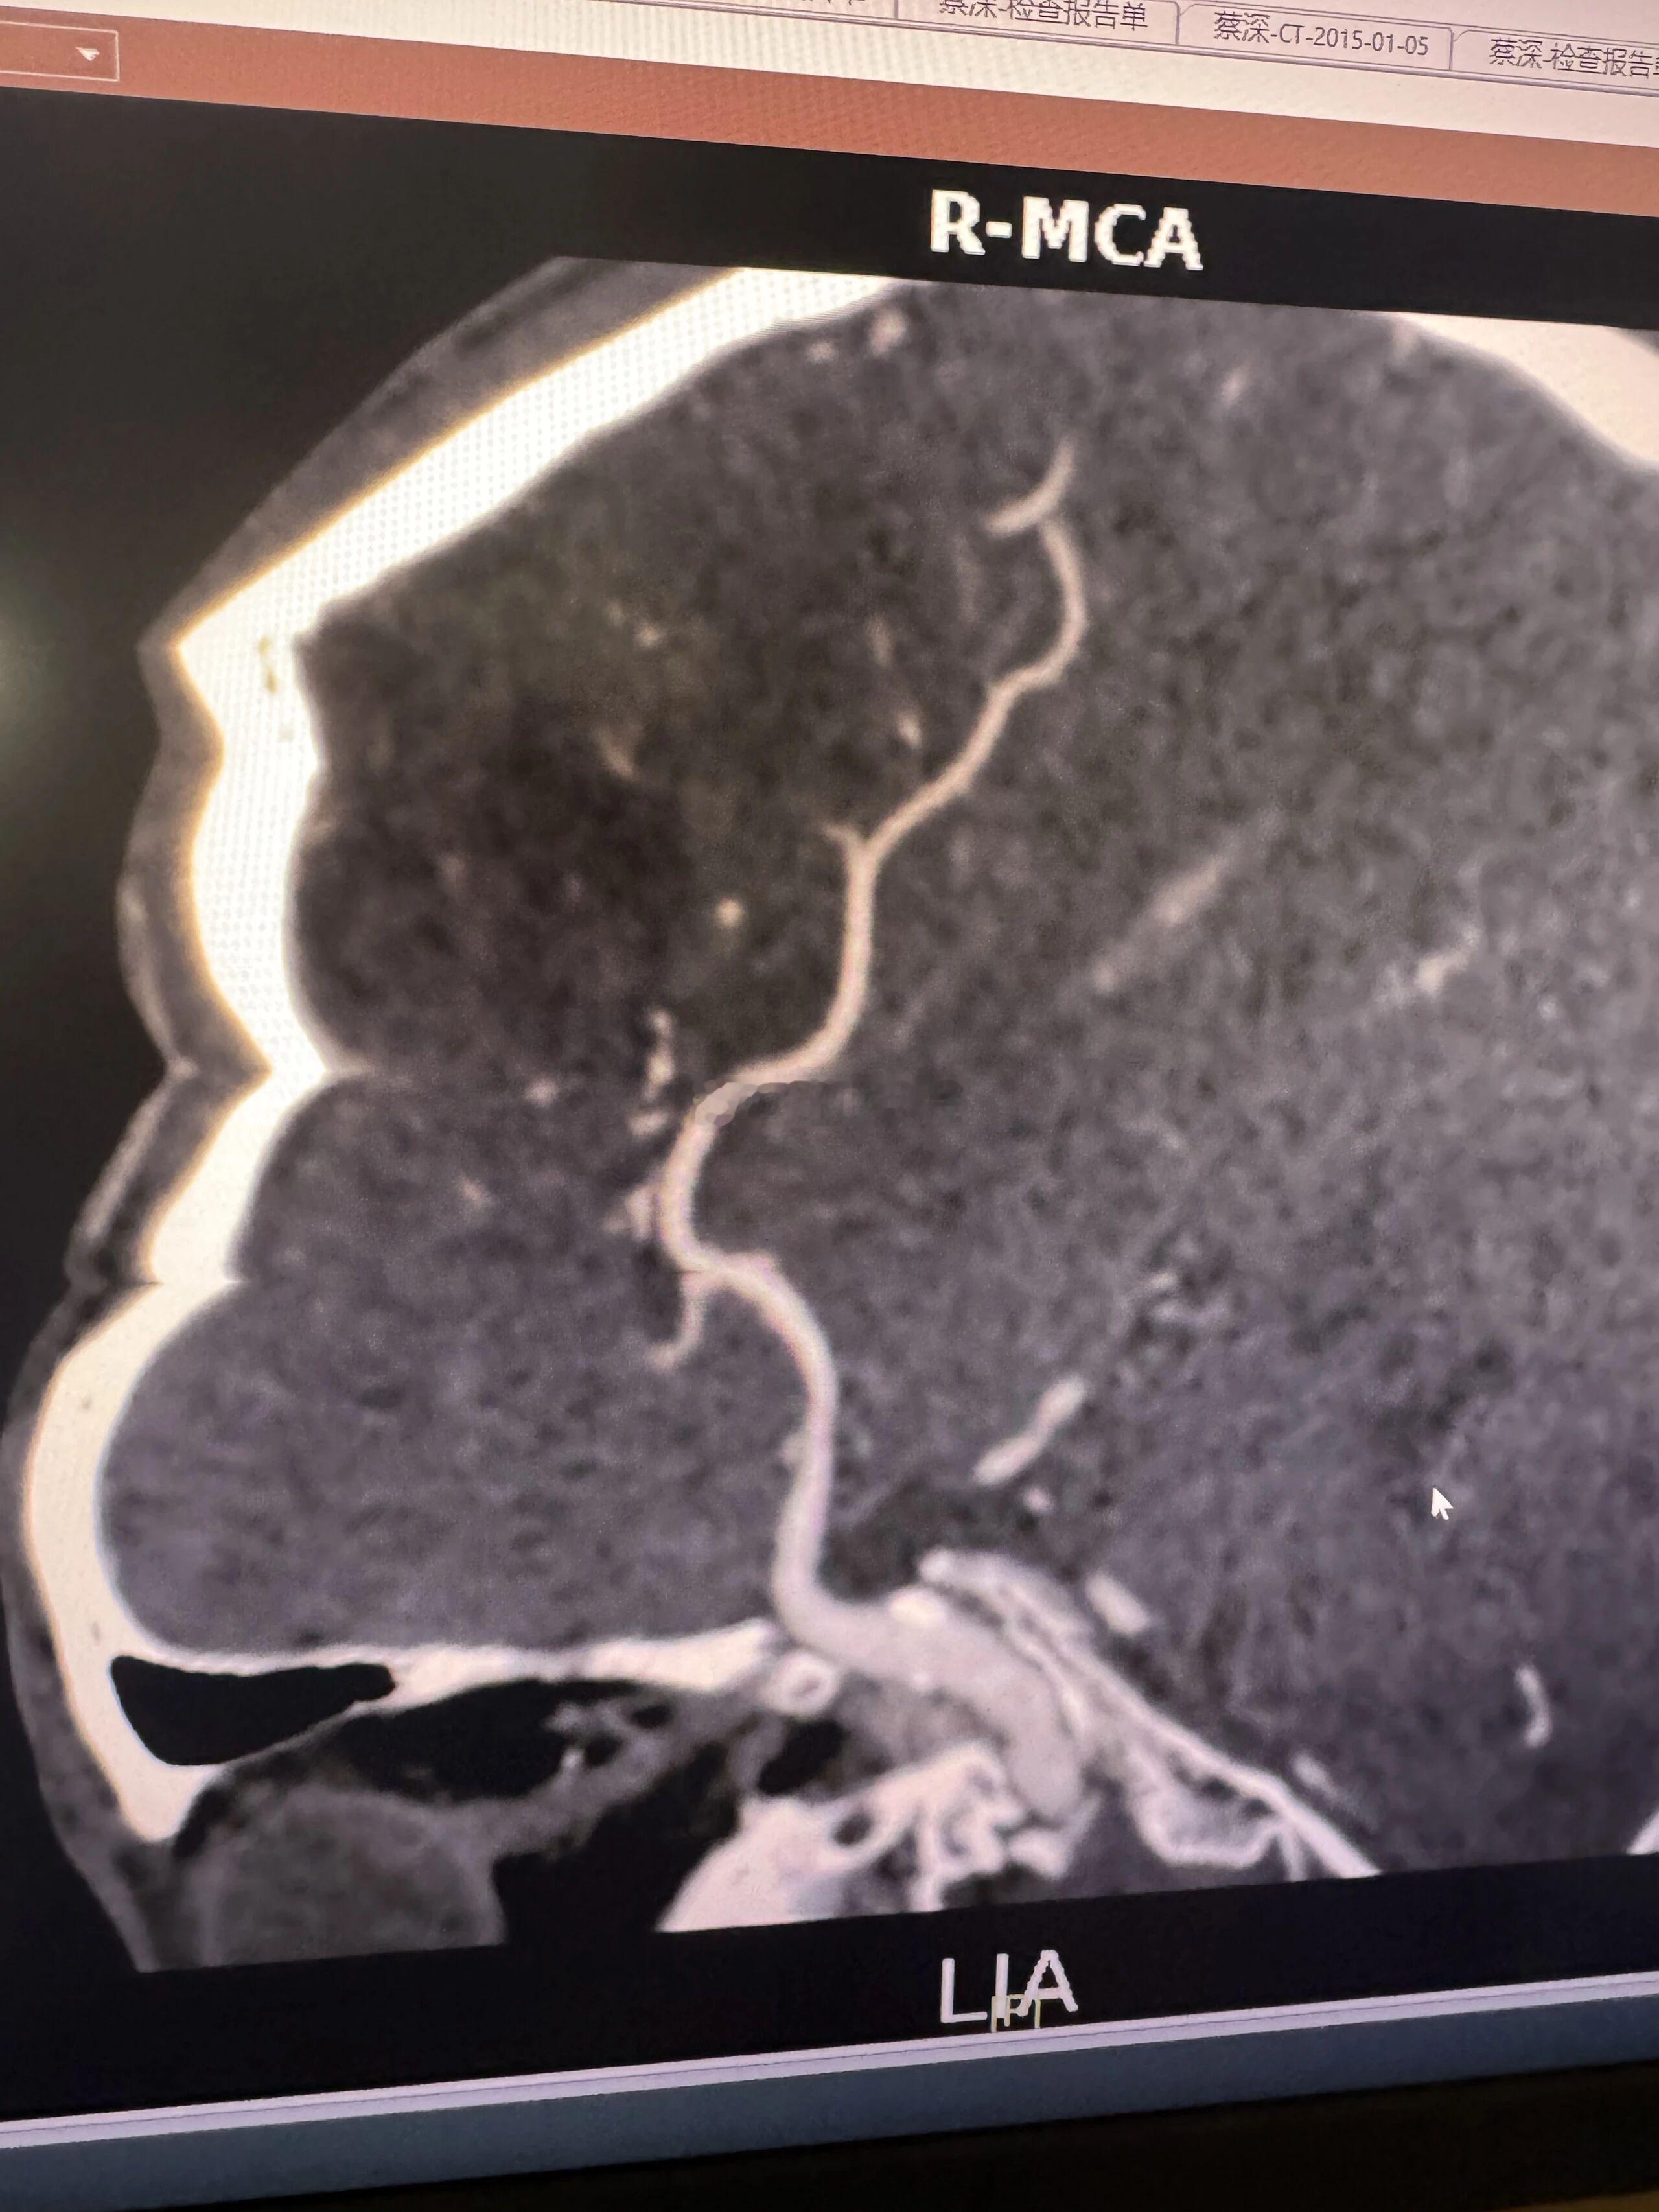

上上周跟颜老师门诊抄方,老师聊到她刚见的一位同学,谈到对手术的看法,老师这位同学大意是能解决问题的话,能不手术最好,除非万不得已,很多时候手术不是终点,后续可能还有很多事情要跟上。这个观点是很中肯的,就拿我从事的脑病来说,颅内血管重度狭窄的患者是否手术要客观评估和分析,是否可以先保守治疗后复查,看看是否有改善,而不是上来就谈手术,我们科每年有很多患者保守治疗后明显改善的,当然也有效果不理想的,比如斑块的性质,有些患者的斑块是机化钙化了的,还有个体差异等,不是说只看医生的水平。今天看到广东省中医院郭建文老师发的一个病例,右侧大脑中动脉M1段重度狭窄(图1、2),经过中西医结合治疗1年复查,基本正常了(图3、4)。